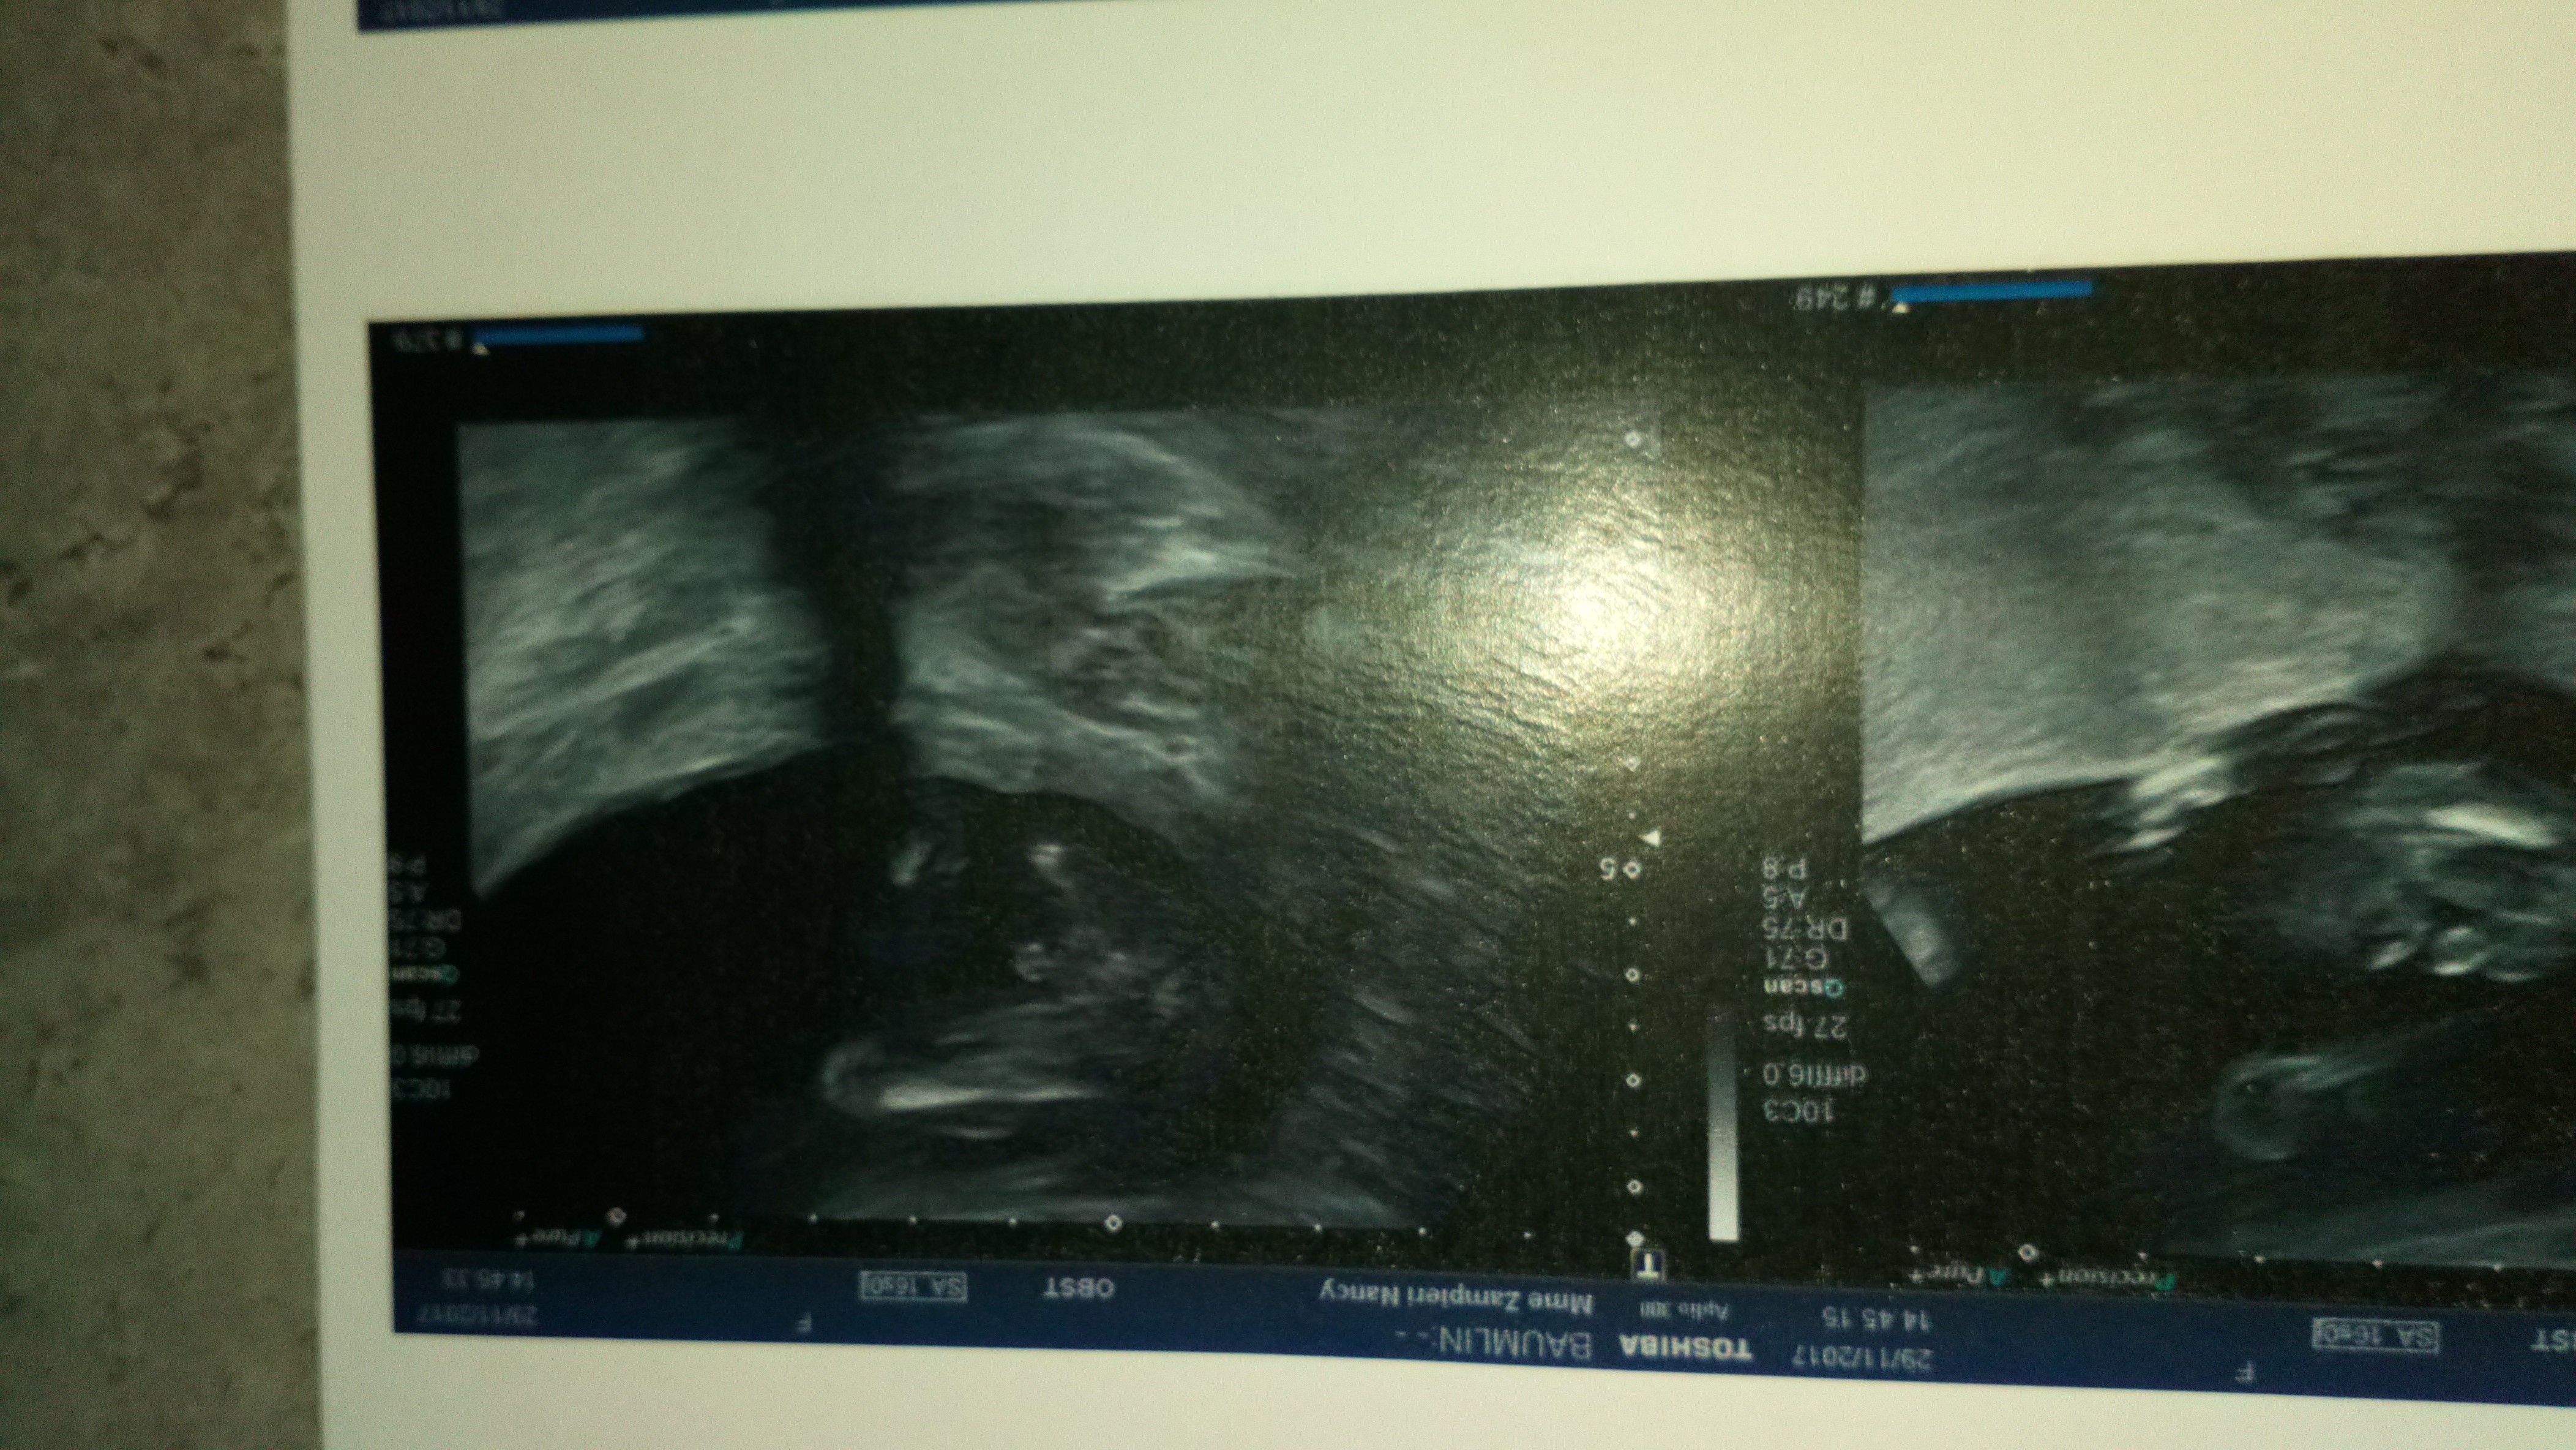

Lors de la première échographie limage affichée nest pas forcément très claire.

Tous les psychologues saccordent à dire que lainé ne doit pas assister à léchographie. Léchographie de datation peut se tromper dune semaine pas plus. En general les echographes se trompe pas si ils voient un garçon mais pour une fille ils peuvent se tromper et dire que c une fille alors qua la prochaine echo ils voient un zizi donc c un garçon.

Vu que cétait une fille à 19sg et confirmation en vrai dans. En principe à ton stade il ne se trompe pas. Mais le plus souvent cest lors de la deuxième échographie que le sexe est connu.